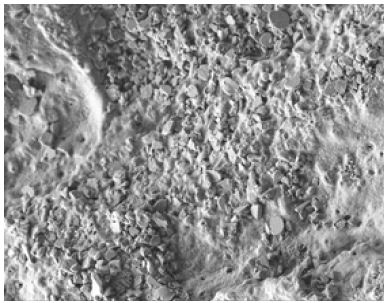

The most important aspect of management is prevention of aetiologies, as discussed above. There have been numerous suggested treatments to alleviate dentine hypersensitivity. Often these treatments will focus on blocking the neural transmission or act as an occluding agent i.e. blocking the dentine tubules [56]. The latter has allowed better management by focusing on the aetiology i.e. dentine tubule exposure as follows. Figure 2 demonstrates the surface of dentine with dentine tubules occluded and covered following tubule occluding toothpaste application (Table 1).

Figure 2: 1000x scanning electron microscopy image of the surface of dentine following dentine tubule occluding toothpaste application.